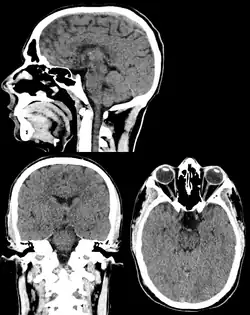

Head & Neck Imaging

.png)

CT scan remains the cornerstone imaging modality for the initial evaluation and subsequent management of patients with acute traumatic brain injury due to its rapid acquisition time and high sensitivity for detecting hemorrhagic complications, such as intraparenchymal hematomas and subdural hemorrhages.[56] CT scan of the head is typically used to detect infarction (stroke), tumors, calcifications, haemorrhage.[57] Tumors can be detected by the swelling and anatomical distortion they cause, or by surrounding edema. CT scanning of the head is also used in CT-guided stereotactic surgery and radiosurgery for treatment of intracranial tumors, arteriovenous malformations, and other surgically treatable conditions using a device known as the N-localizer.[58][59][60][61][62][63]

Contrast CT is generally the initial study of choice for neck masses in adults.[64] CT of the thyroid plays an important role in the evaluation of thyroid cancer.[65] CT scan often incidentally finds thyroid abnormalities, and so is often the preferred investigation modality for thyroid abnormalities.[65]